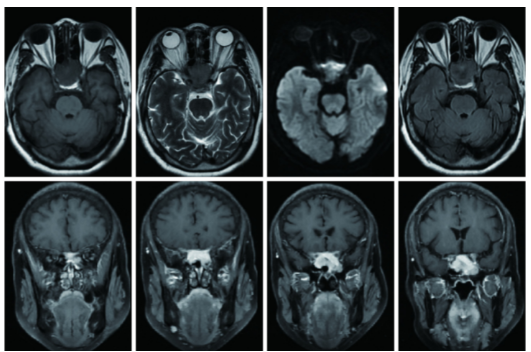

血细胞分析、C反应蛋白、红细胞沉降率、降钙素原、凝血常规、血电解质、肝肾功能、血清肌钙蛋白T测定、血清乳酸脱氢酶、β2-微球蛋白、HIV抗体/抗原等未见明显异常。头颅CT示鞍区稍低密度影,考虑占位性病变;头颅MRI示蝶窦内异常信号,建议副鼻窦强化扫描,MRA示脑动脉硬化,MRV未见异常;垂体MRI示鞍区占位累及海绵窦及蝶窦;鼻窦增强MRI示T1WI呈等信号,T2WI呈等信号,DWI呈稍高信号,Flair呈等信号,增强扫描后可见明显强化,累及两侧海绵窦,鞍底塌陷,正常垂体未见显示,双侧上颌窦、蝶窦粘膜增厚,明显强化,考虑垂体大腺瘤(图1)。

图1 患者鼻窦MRI检查结果

鞍区可见占位性病变,累及海绵窦及蝶窦,T1WI呈等信号,T2WI呈等信号,DWI呈稍高信号,Flair呈等信号,增强扫描后可见明显强化,累及两侧海绵窦,鞍底塌陷,正常垂体未显示,双侧上颌窦、蝶窦粘膜增厚,明显强化。

当患者出现神经系统症状时应接受诊断性脑部影像学检查,MRI是首选的成像方式。PCNSL影像学表现为孤立性病变或多灶性病变。PCNSL病变在T1WI图像上呈等信号至低信号,在T2WI图像上呈等信号至高信号,并均匀增强。病灶通常仅被中等程度的水肿包围,并且经常局限于弥散加权图像上。

病灶强化形态多样,典型强化形态可为脐凹征、缺边征(亦称咬征)、劈裂征、马蹄征、鼠尾征、握拳征、尖角征、蝶翼征及卫星征等。本例患者病灶较大且位于鞍区,受周围组织挤压,影像学形态不典型。立体定向或者开放性脑活组织检查为临床诊断PCNSL的金标准。